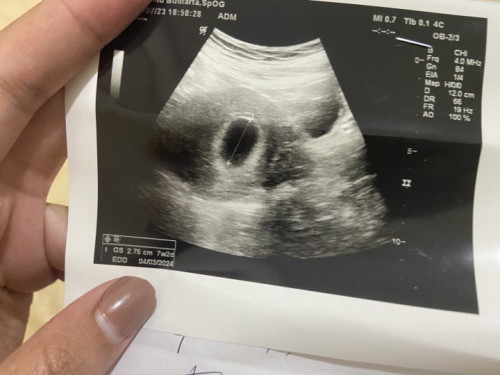

Bun ini 7 week 2 days kok janinnya belom keliatan yaa? Apakah wajar??

7 week 2 day

Itu usg perut atau tranvaginal bun? Kebetulan kemaren aku baru usg usia kehamilan sama dengan bunda. Waktu di usg perut janin nya juga belum keliatan jadi dokter nyaranin untuk usg transvaginal. Habis di usg transvaginal baru keliatan janin dan djj nya

usg 2d apa transv kak? kalo usg 2d biasanya belum keliatan. kemaren aku usg transv alhamdulillah keliatan. biasanya dokter selalu rekomendasi buat yg dibawah 9weeks enaknya usg trans v, yaa walopun ga nyaman dikit + malu si

Ini punyaku kemarin usg di 6w5d sudah kelihatan tp ya memang masih kecil bgt bun ukurannya. Next usg lagi aja bun, insyaaallah si janin pasti kelihatan

sama bun saya juga trakhir usg 7week1day belum ada janin nya, gs saya malah 2,90cm